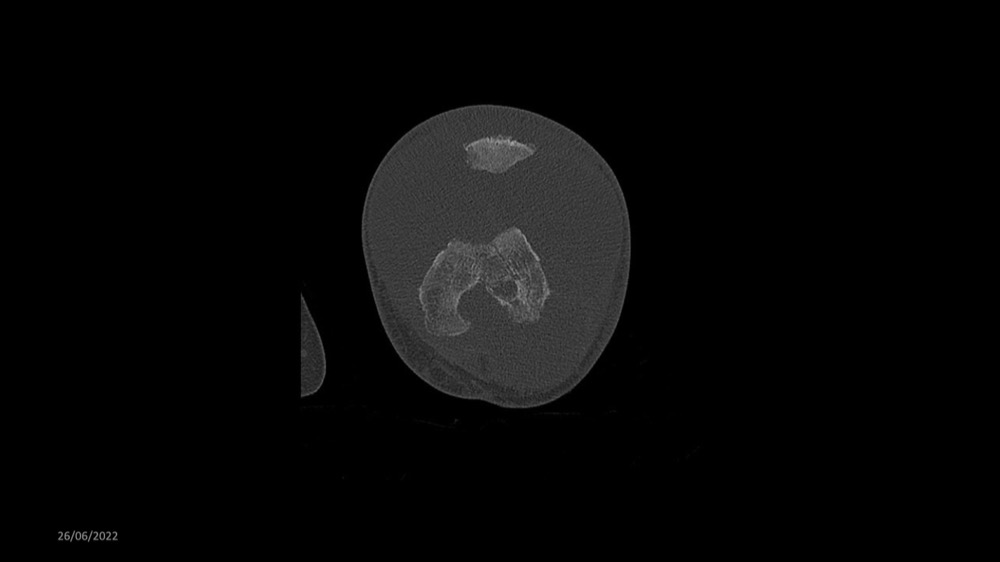

Reichert / Amar / Tordjman / Carlier 29/06/2022